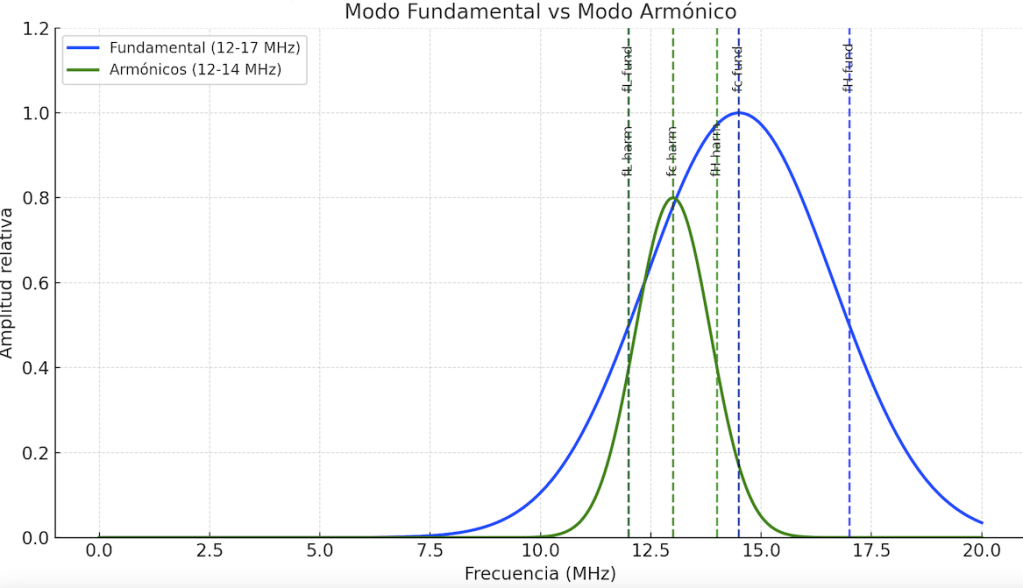

Exploración ecográfica

El estudio ecográfico longitudinal y transversal del compartimento posterior superficial muestra:

- Rotura de la aponeurosis del gastrocnemio medial (GA) con afectación extensa de la aponeurosis libre (FGA).

- Presencia de hematoma intermuscular parcialmente organizado, con septos internos bien definidos que indican fase no aguda del proceso.

- Retracción parcial del vientre muscular del gastrocnemio medial.

- Conservación de la continuidad distal con el tendón de Aquiles.

- Asincronía visible entre gastrocnemio y sóleo durante maniobras dinámicas de dorsiflexión y plantiflexión.

- Microvascularización intramuscular visible en modo Doppler en las fibras retraídas, indicativa de actividad reparativa.

- En la imagen de elastografía de strain, se evidencia menor rigidez en la zona del hematoma, como es esperable, y mayor rigidez en las fibras retraídas, que se comportan de forma más fibrosa y densa en la fase de cicatrización.

- Panoramic View se observa la longitud y extensión de la zona afecta

Clasificación

Según la clasificación ecográfica de Balius-Pedret (2020), la lesión corresponde a un Tipo 4, caracterizado por la afectación combinada de la aponeurosis del gastrocnemio (GA) y de la aponeurosis libre (FGA), con retracción del vientre muscular y hematoma intermuscular.

Este tipo de lesión se asocia a un mayor tiempo de recuperación funcional y riesgo de fibrosis residual o asincronía persistente gastrocnemio-sóleo.